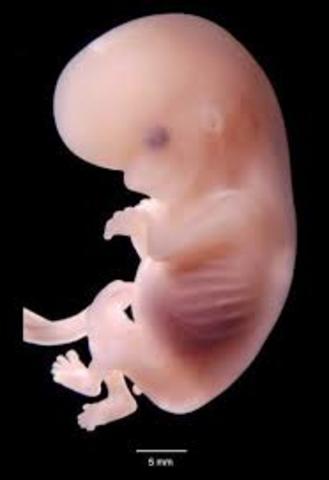

• Semana 8

Semana 8

Todos sus órganos mayores se han formado, aunque no completamente. Su cola embrionaria desaparece. El cerebro está completamente creado y las neuronas empiezan a dividirse formando el sistema nervioso.